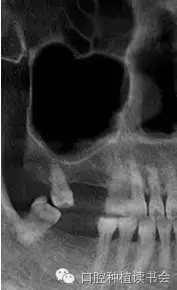

上頜竇氣化的現(xiàn)象主要來自先天因素和生理病理性因素,有的病人雖然年輕,但上頜竇腔較大,后牙牙根幾乎伸進(jìn)上頜竇。隨著年齡增大、磨牙缺失,由于上頜竇處于負(fù)壓狀態(tài),尤其是缺牙后缺少來自牙槽脊的功能刺激,氣化現(xiàn)象會更嚴(yán)重,加之原有竇腔較大,就表現(xiàn)為巨大的上頜竇腔,甚至竇底與鼻底在同一水平(圖2)。有研究表明,上頜竇容積在青少年階段隨年齡而變化,中老年階段達(dá)到穩(wěn)定狀態(tài),氣化系數(shù)無增齡性改變。上頜竇竇腔平均最大容積為:38*33*38mm(Chih-Long,2014)。上頜竇容積和牙槽骨骨量呈負(fù)相關(guān),上頜牙全部脫落促進(jìn)上頜竇變形,上頜竇容積有減小趨勢。上頜骨的老化特點(diǎn)是一個漸變的過程,步入中年期開始進(jìn)行重塑,而老年期上頜骨形態(tài)變化較小。

▲(圖2)